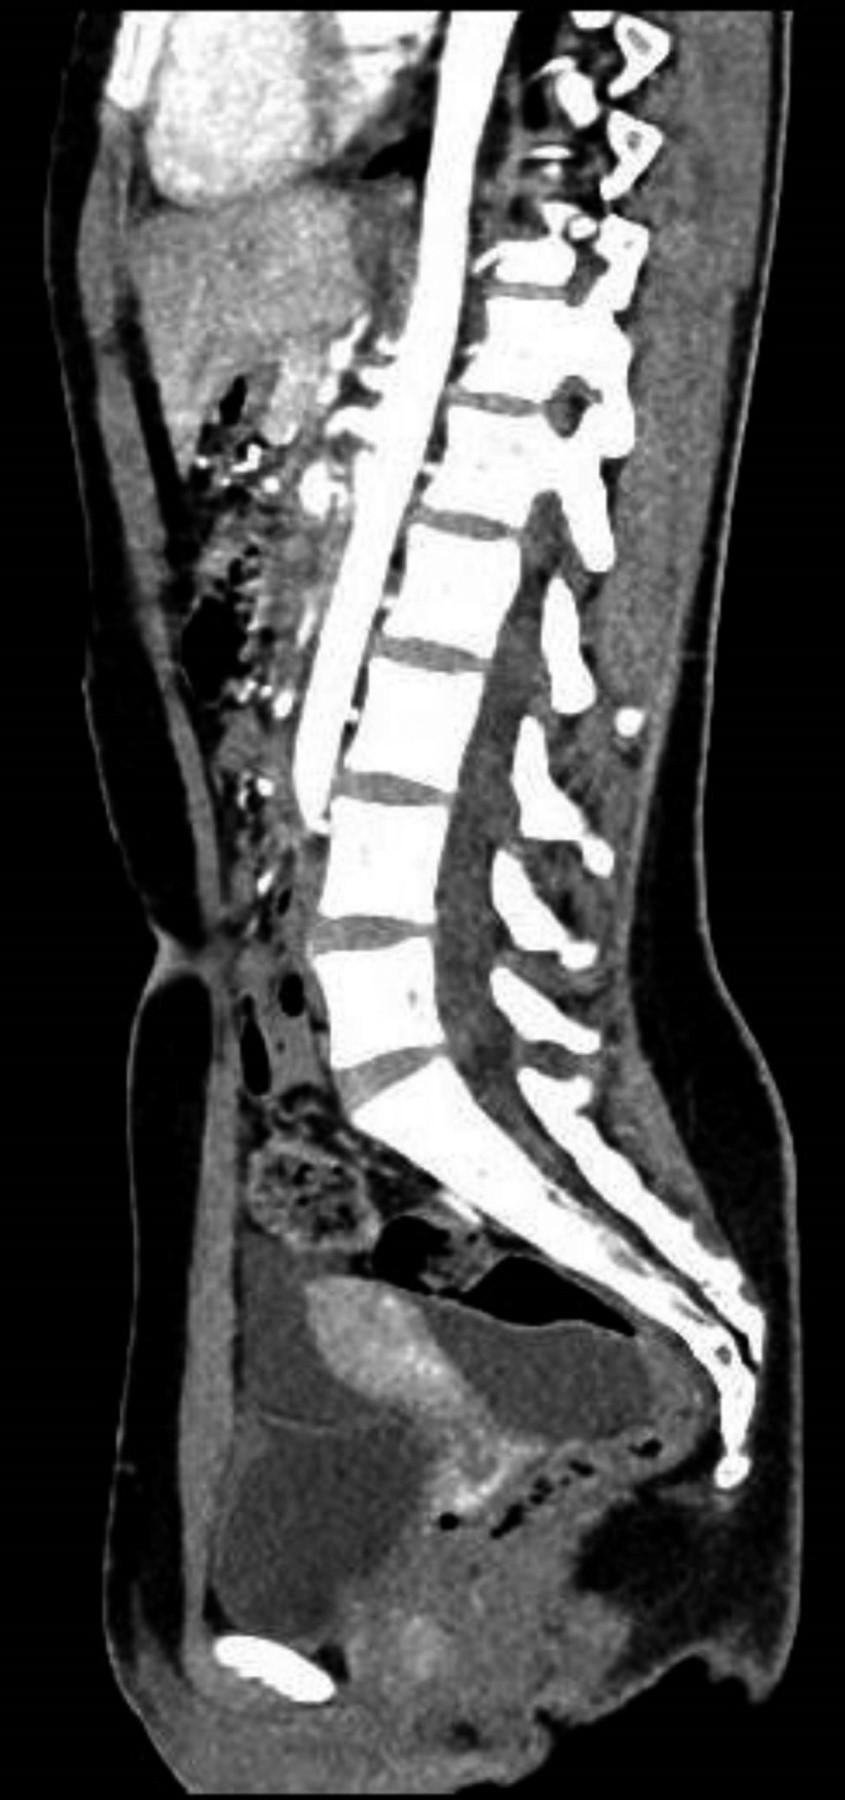

Cita de seguimiento a las tres semanas, con ultrasonido de control, el cual reportó líquido en ambas fosas iliacas y fondo de saco, con presencia de finos septos adyacentes a anexos, comparando con estudio previo se encontró aumento de volumen, resto de órganos pélvicos normales (Figura 1). Se internó por urgencias para complementar su estudio con tomografía axial computarizada de abdomen con contraste intravenoso, reportando abundante líquido libre en hueco pélvico y corredera parietocólica derecha (Figuras 2 y 3). Fue valorada por los servicios de cirugía general y ginecología y obstetricia, programándose para laparoscopía diagnóstica.

La ecografía y la tomografía computarizada (TC) son útiles en el abordaje inicial, revelan masas multiloculadas con tabiques gruesos que desplazan los órganos vecinos sin invadirlos; con todo, estos hallazgos están lejos de ser específicos en MPMB, con sensibilidad entre 15-30%. La resonancia magnética (RM) es el estudio con mayor sensibilidad (99%), mostrando señales hiperintensas que reflejan líquido quístico, con realce de los tabiques. En todas las modalidades de imagen se puede observar líquido libre y engrosamiento peritoneal discreto, en contraste con el mesotelioma peritoneal maligno, que frecuentemente se presenta con ascitis franca y engrosamiento peritoneal difuso.5